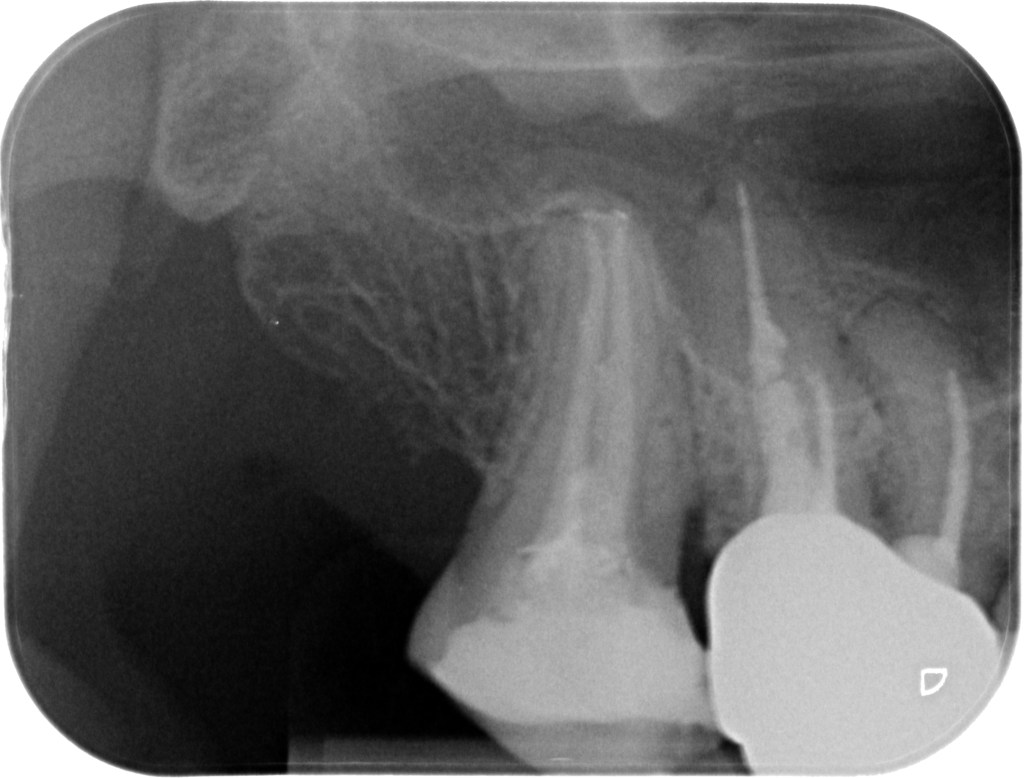

10.04.2025 Patientin JL, geb. am 21.07.1981, Zahn 17, WF- Kontrolle